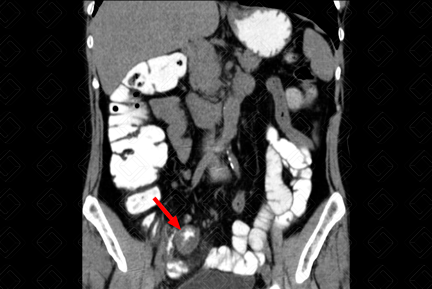

Texto alternativo para a imagem Figura 2. Créditos: Dra. Elazir Mota - Rio de Janeiro/RJ

Descrição das figuras 1 e 2: Ultrassonografia do abdome. Paciente jovem com queixa de dor na fossa ilíaca direita e febre iniciada há dois dias. Realizou ultrassonografia do abdome na emergência, evidenciando apêndice espessado, medindo 0,9 cm, não compressível e com aumento da vascularização parietal ao Doppler colorido (figura 1). Observa-se, ainda, presença de apendicolito na sua extremidade, caracterizado por imagem ecogênica com sombra acústica posterior (figura 2 - setas brancas).